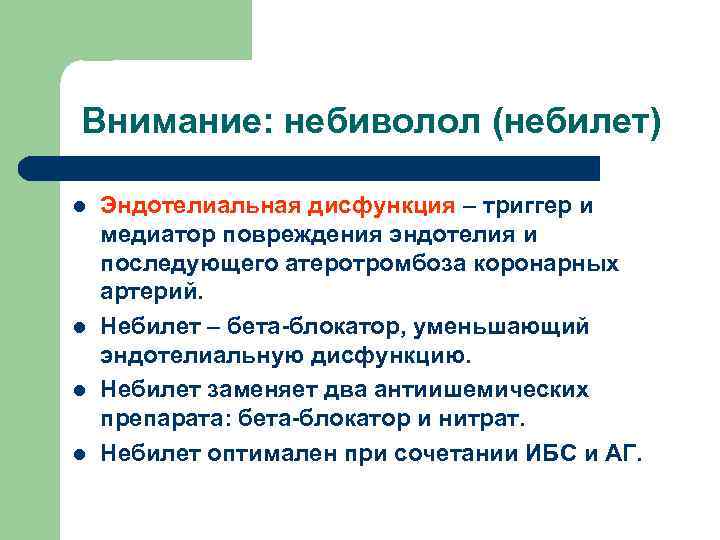

Внимание: небиволол (небилет) l l Эндотелиальная дисфункция – триггер и медиатор повреждения эндотелия и последующего атеротромбоза коронарных артерий. Небилет – бета-блокатор, уменьшающий эндотелиальную дисфункцию. Небилет заменяет два антиишемических препарата: бета-блокатор и нитрат. Небилет оптимален при сочетании ИБС и АГ.